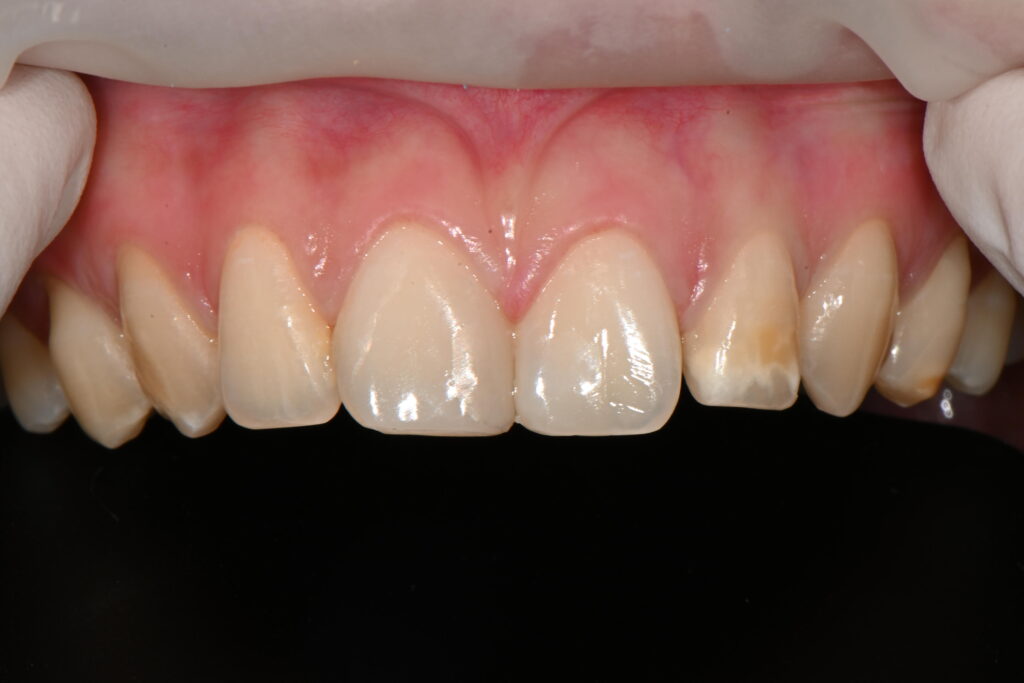

피니싱과 폴리싱을 마친 과정

최종적으로 피니싱과 폴리싱이 완성된 결과입니다

둘 사이에 적절히 채워진걸 확인이 가능하구요

여기서 제일중요한 부분은

잇몸사이입니다

갑자기 채워진 치아의 경우

가운데 잇몸에 염증이 생실수도 있기때문에

다이아스테마 치료를 받으신 분들은

앞니 사이에 잇몸부위 염증이 생기지 않도록 조심하고 관리를 해야합니다

치료 전후 앞쪽과 뒷쪽을 확인하여

완전히 치아의 형태를 재현하였는지 확인을 해야 합니다

치료전후를 보면

뒷쪽까지 완전히 충전이 되면서

치아의 모양을 재현하였습니다